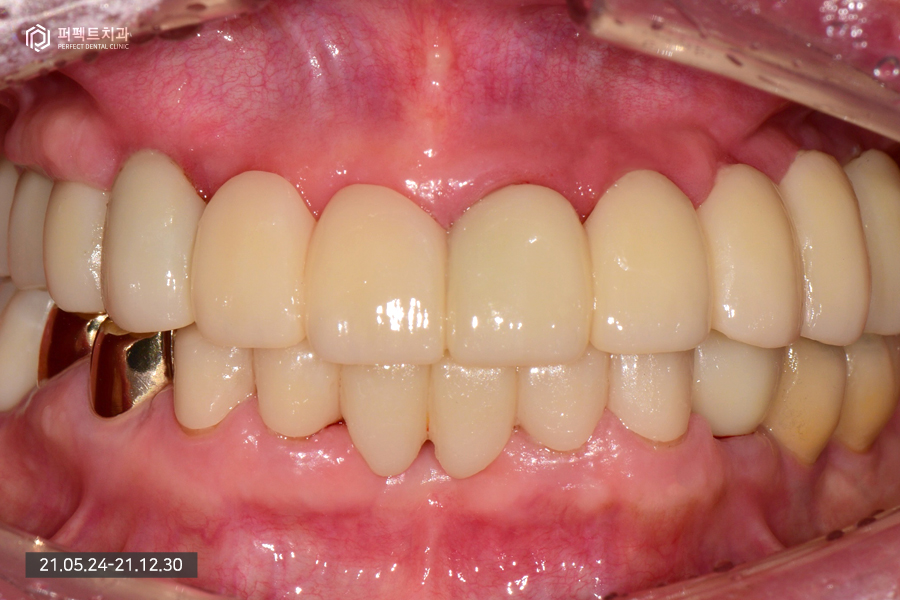

위 환자분의 경우 뼈가 굉장히 약한 뼈이기도 하고 골다공증도 있으셔서 심을 수 있는 곳에 가능한 많은 임플란트를 식립하기로 하였습니다. 완성된 사진을 보면 더 명확히 아실 수 있는데요.

전악임플란트를 하신 부분을 확인해보시면 세덩어리로 완성을 했습니다. 오른쪽 파랗게 보이는 부분은 홀을 임시로 메워둔 상태입니다. 완성된 사진을 보시면 잘 치료된 것을 보실 수 있을 것입니다.

오늘은 80대 환자분의 임플란트 식립 과정을 살펴보았는데 굉장히 쉬워 보이지만 실제로는 어려운 케이스 였습니다.

그 이유는 첫번째, 임플란트 식립 환경이 좋지 않았기 때문입니다. 환자분은 골다공증도 있으셨고 뼈가 너무 물러서 임플란트를 식립할 수 없는 자리도 많이 있었기 때문입니다. 그러다보니 환자분께서는 임플란트를 식립할 수 있는 곳에는 임플란트를 식립하길 원하셨고 이로 인해 9개의 임플란트 식립, 5개의 치아를 걸어서 14개의 완성된 치아를 갖게 되었습니다.

그리고 두번째로 어려운 점은 위에 치아가 없기 때문인데, 이런 경우 위아래 높이의 기준이 사라지게 됩니다. '고합고경'이라는 말을 쓰는데 위아래 치아가 맞물리는 높이를 설정하는데 굉장히 어려움을 겪게 됩니다. 치아가 한두개만 있더라도 위아래가 물리는 기준점이 있는데 환자분의 경우 1) 치아가 하나도 없고, 2) 틀니 사용도 하지 않기 때문에 위아래 높이를 맞추는 일이 어렵습니다.

그렇지만 요즘에는 디지털화 되고 3d 스캐너와 3d CT를 사용해 환자분이 가지고 있는 처음 높이를 그대로 가지고 올 수 있습니다. 예전 방식 보다는 조금 더 쉽게 완성을 할 수 있었고 임시치아도 다 만들어서 한번 써보았기 때문에 높이가 완전히 맞은 다음 최종 보철을 완성하는 과정을 거치게 되었습니다. 총 치료기간은 7개월로 깔끔하게 마무리가 되었으며 지금도 만족하면서 잘 사용하고 계십니다 ^^